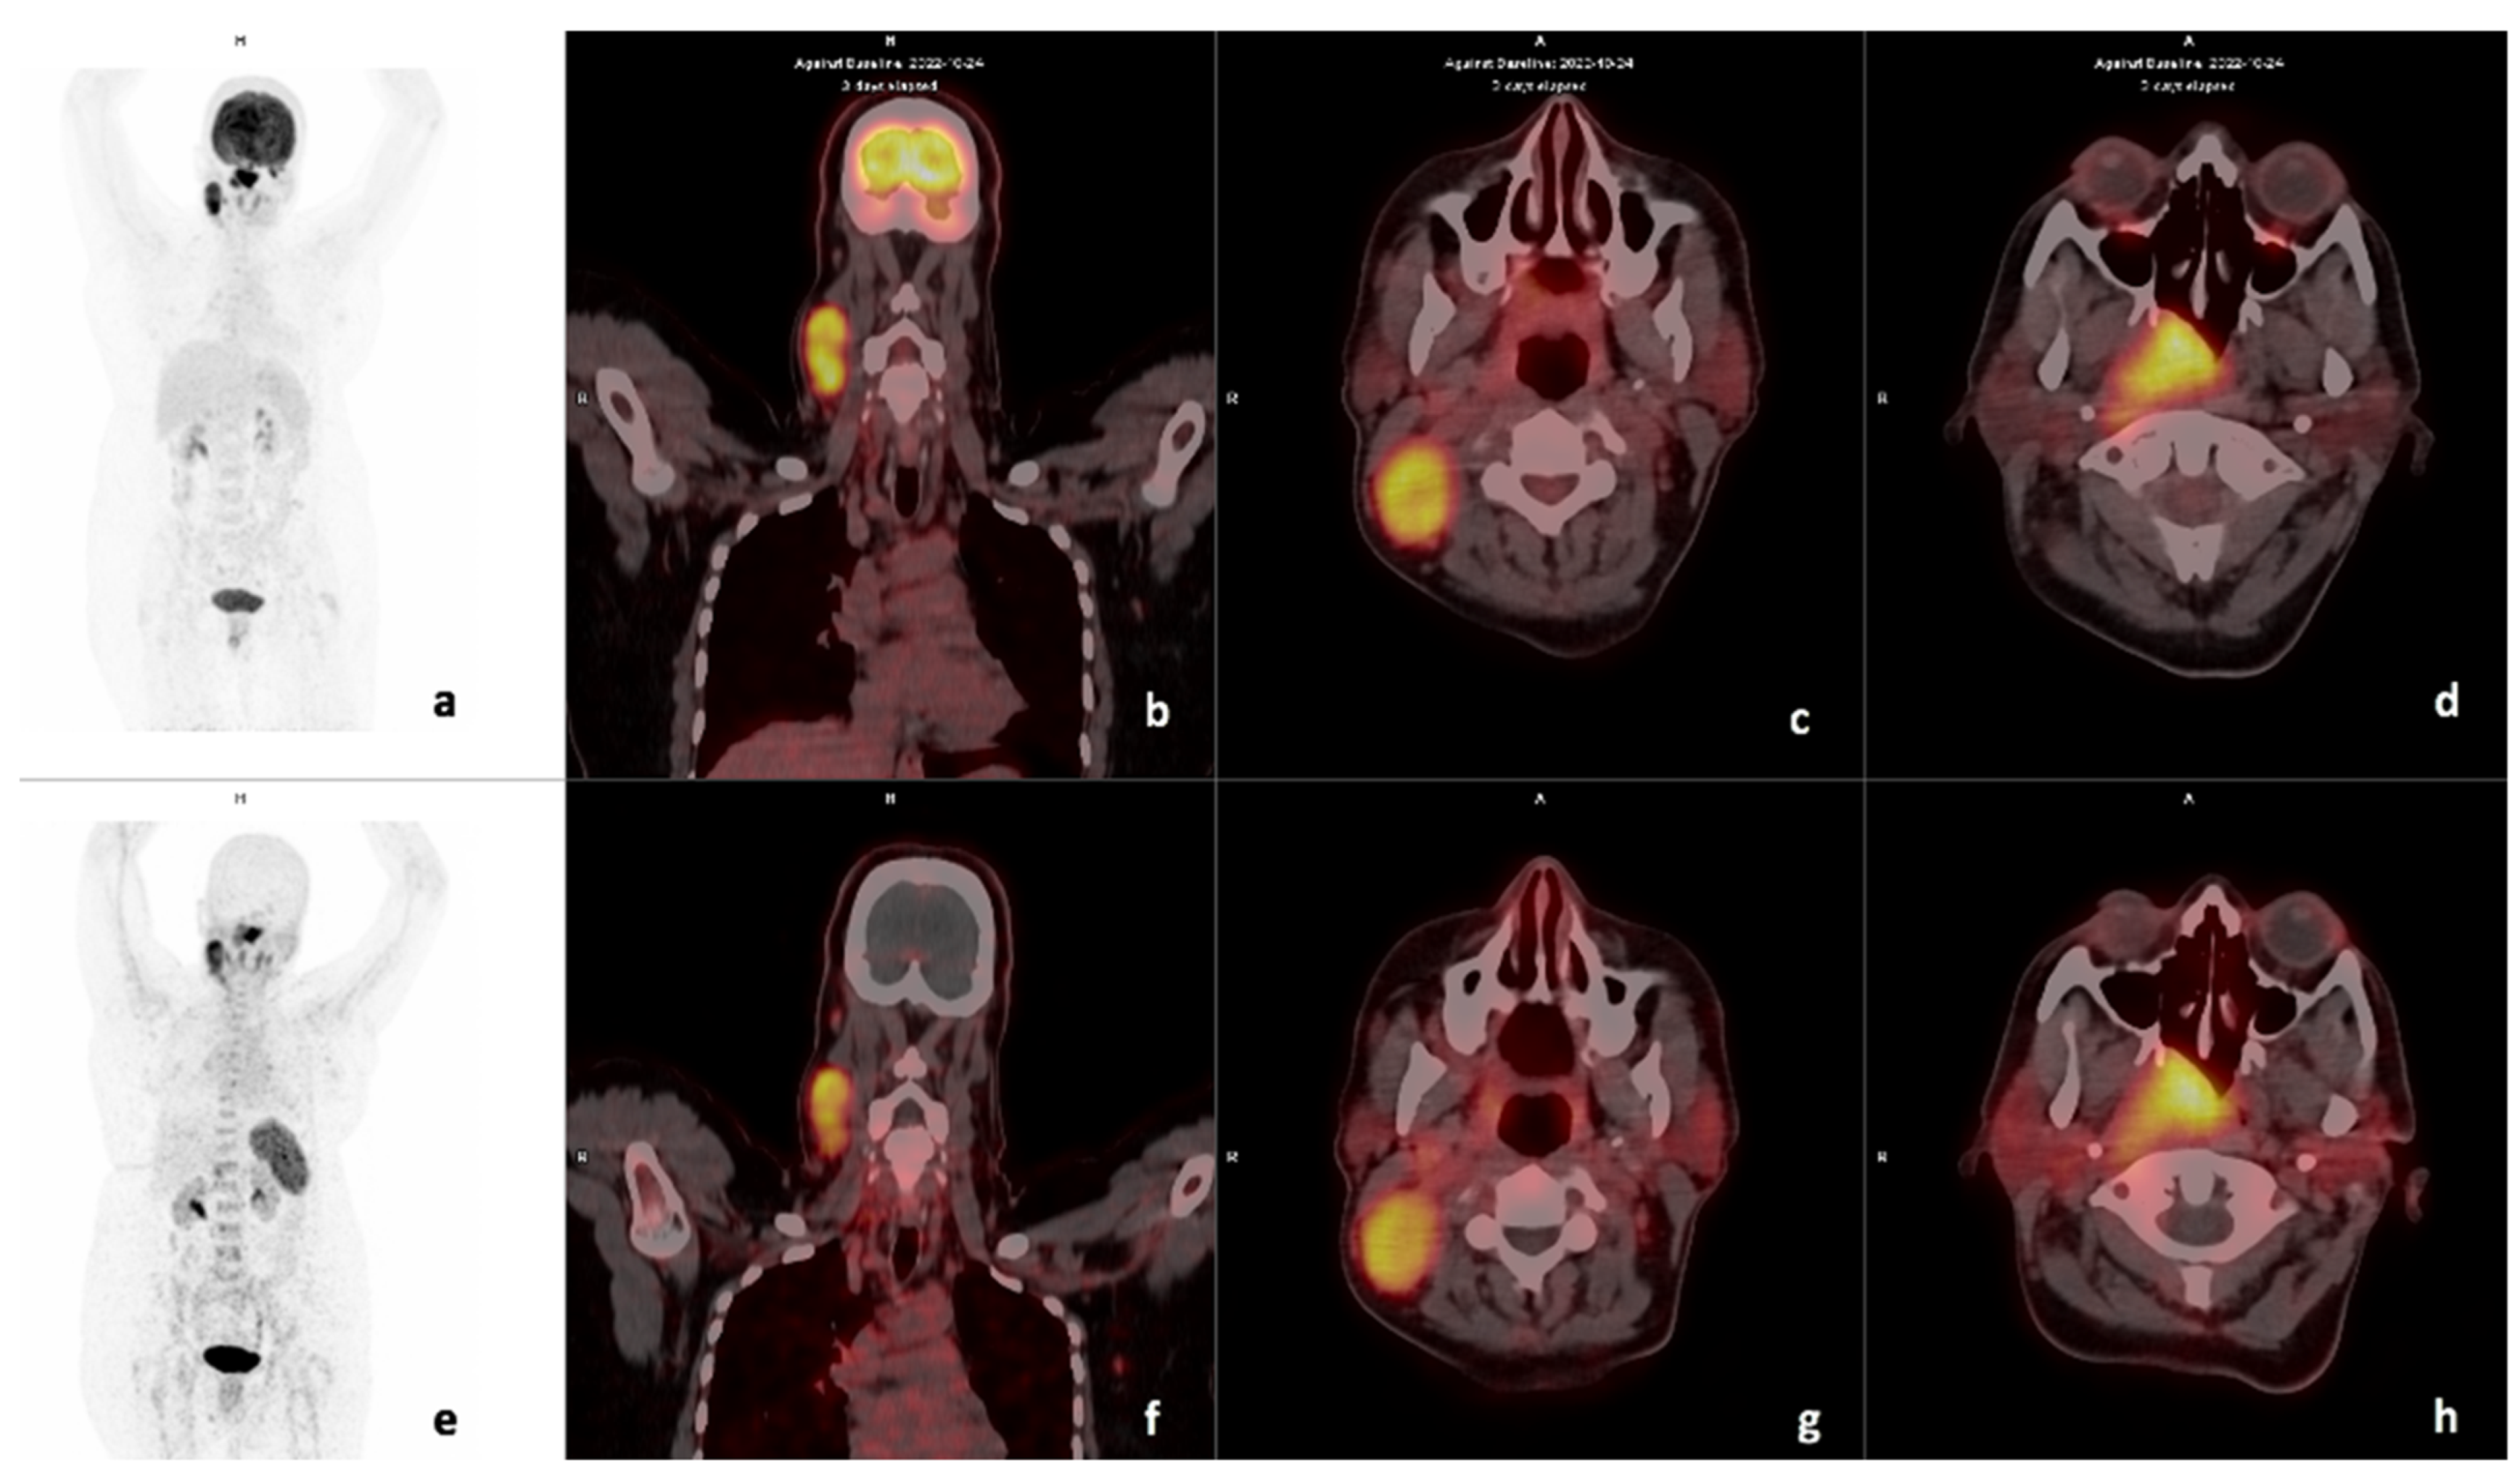

3.2. Comparison of FDG and 68Ga-Pentixafor

3.3. Visual Analysis

3.7. Metastasis